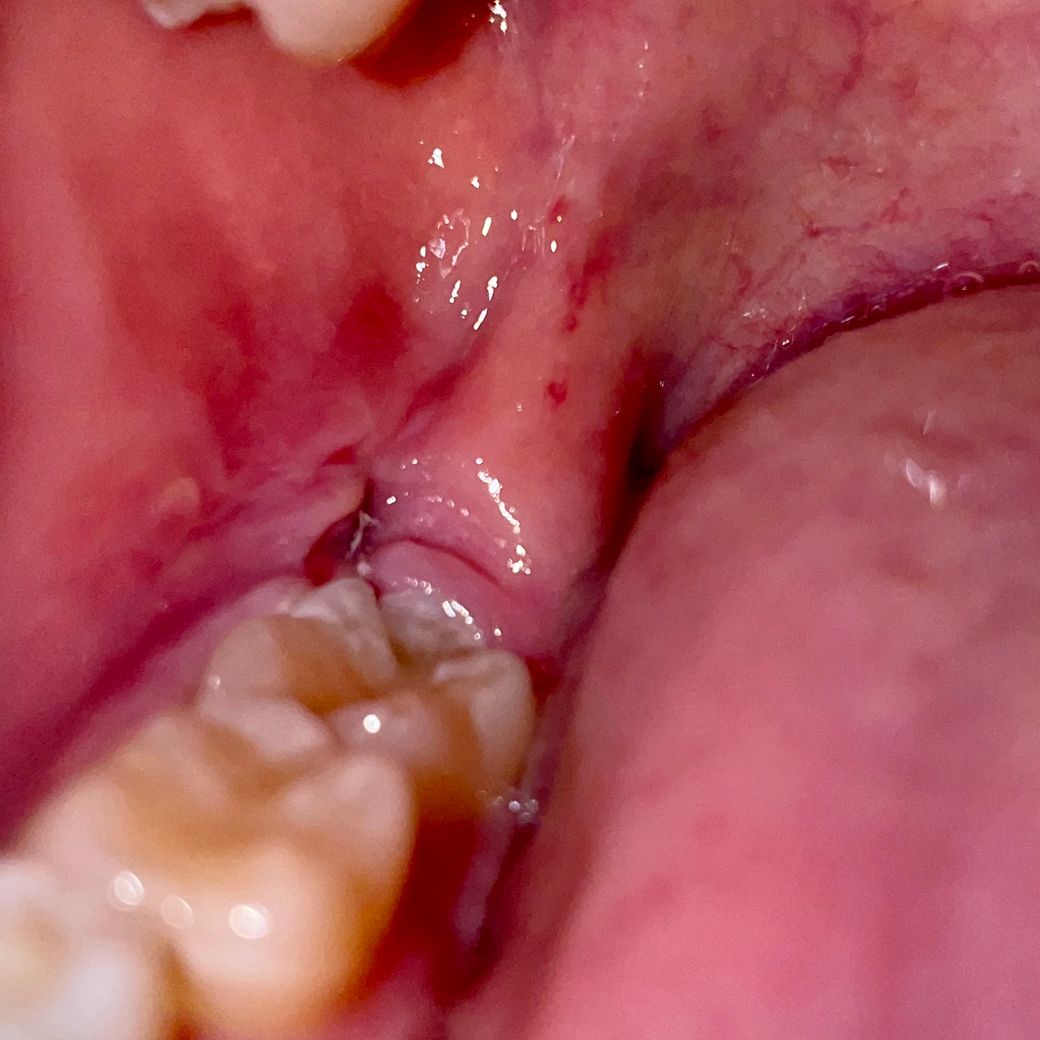

사랑니 발치후 1주일이 되어서 실밥제거를 하였는데 구멍쪽에 음식물인지 잇몸뼈인지 모르겠는데 흰색이 살작 보이는데 음식물인가요 ? 잇몸뼈인가요 ㅠ?

이게 만약 음식물 이라고 가정했을때 못빼고 이상태로 있으면 잇몸구멍 안에 음식물이 들어간채로 그대로 아물게 되나요??? 그러다가 나중에 잇몸속에 묻힌 음식물이 못나오고 썩으면 잇몸을 다시 절개 해야 하는지 ㅠ 걱정되네요

결론은 잇몸이 차오르면서 음식물을 밀어내나요? 아니면 같이 묻히나요? 사진첨부해 봅니다

현재 보이는 흰색 이물질은 사진만으로 판단하기는 어렵지만 뼈의 가능성은 낮습니다. 이물질이라면 일반적으로 세척을 통해 제거되거나 살이 차오르면서 밀려나올 가능성이 많습니다. 그러므로 치과에 내원하시어 진료를 받아보시는 것이 좋겠습니다.

발치한 부위에 막이 형성된것입니다. 피부에 상처가 나서 딱지가 생기기 전 상태라고 생각하면 되겠습니다.